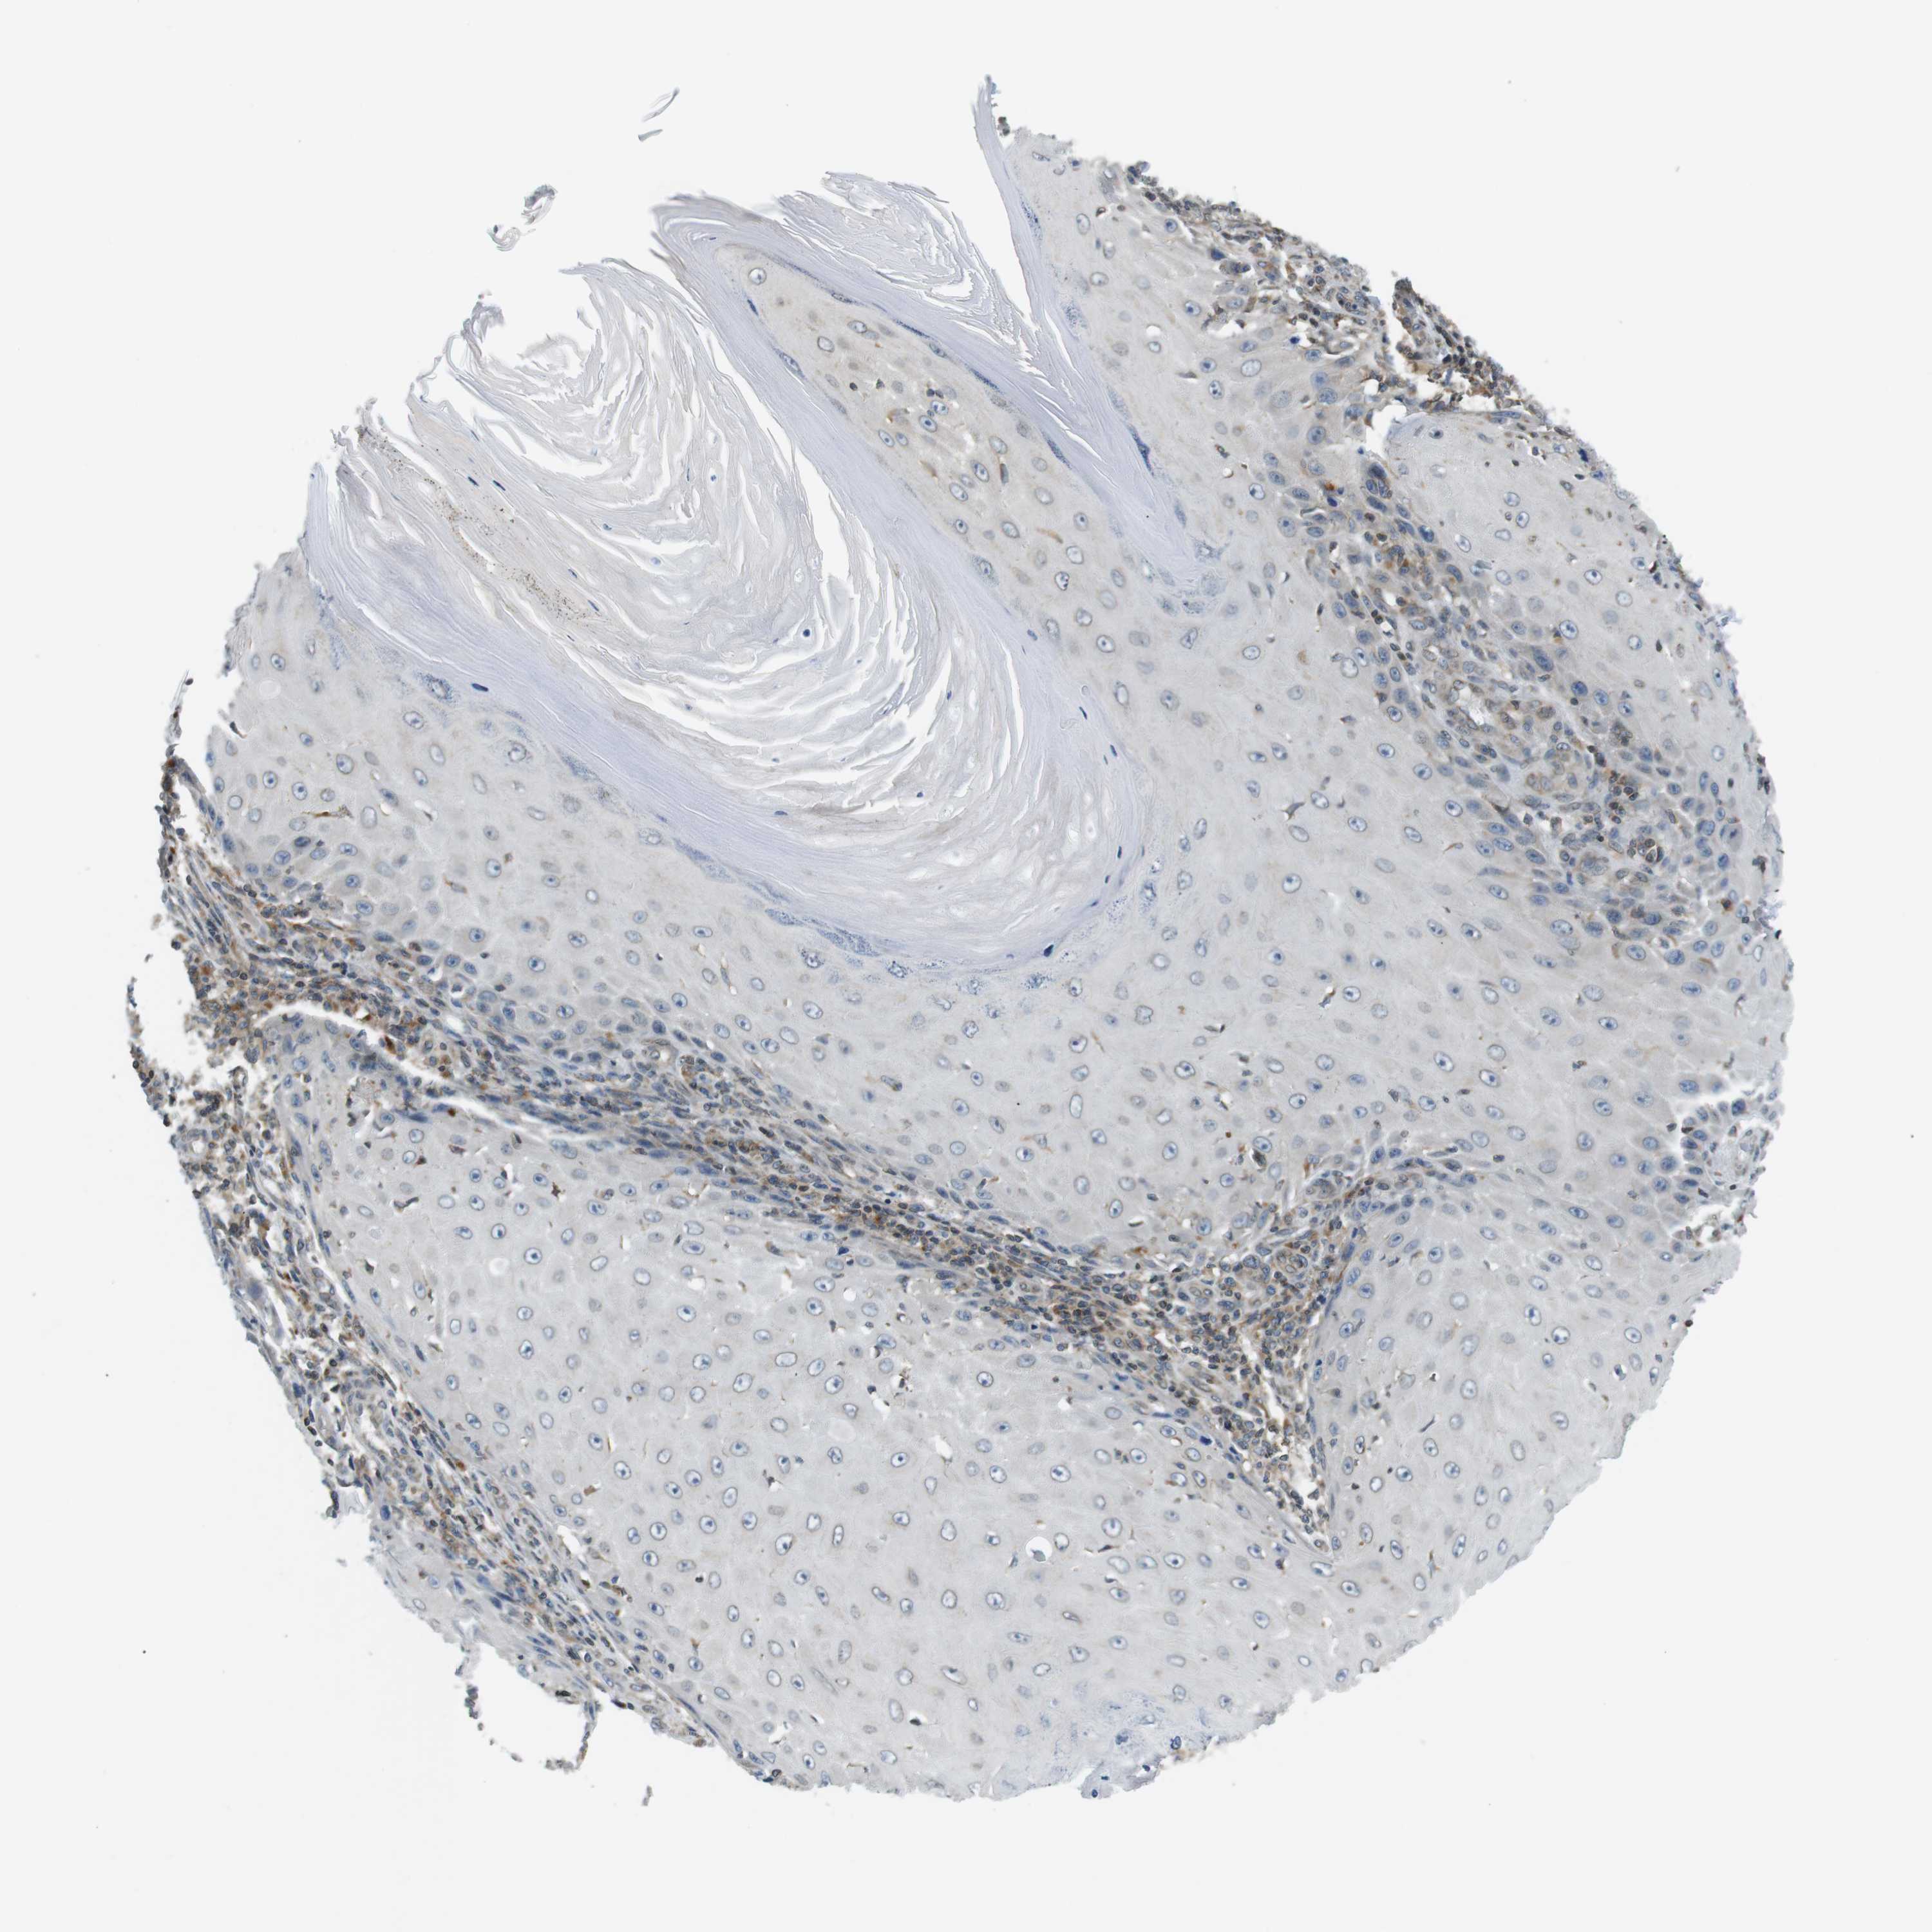

SKIN CANCER - Protein expressioni

A mouse-over function shows sample information and annotation data. Click on an image to view it in a full screen mode. Samples can be filtered based on level of antibody staining by selecting one or several of the following categories: high, medium, low and not detected. The assay and annotation is described here.

Each image is clickable and will lead to virtual microscopy that enables deeper exploration of all samples and also displays staining intensity scores, fraction scores and subcellular localization as well as patient and tissue information for each sample.

Antibody HPA000399

Staining

High

Intensity

Strong

Quantity

>75%

Location

Nuclear

Squamous cell carcinoma, NOS